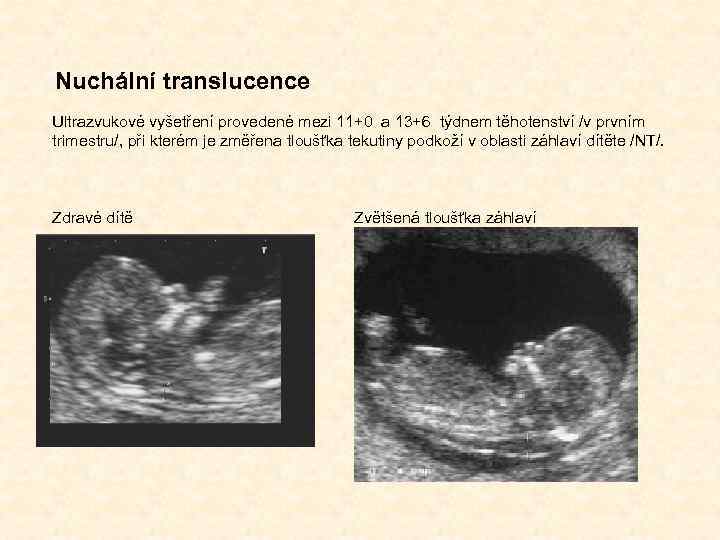

Nuchální translucence Ultrazvukové vyšetření provedené mezi 11+0 a 13+6 týdnem těhotenství /v prvním trimestru/, při kterém je změřena tloušťka tekutiny podkoží v oblasti záhlaví dítěte /NT/. Zdravé dítě Zvětšená tloušťka záhlaví